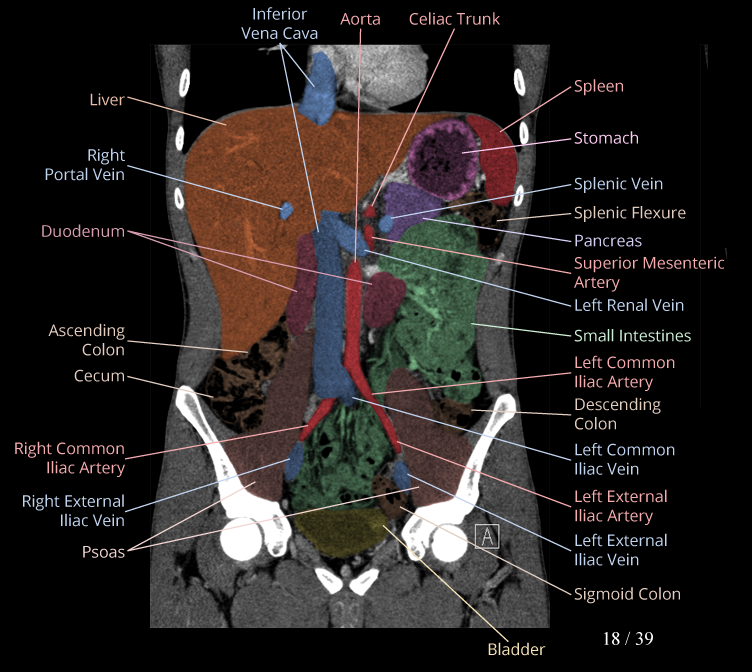

Body

Covers abdominal CT anatomy.